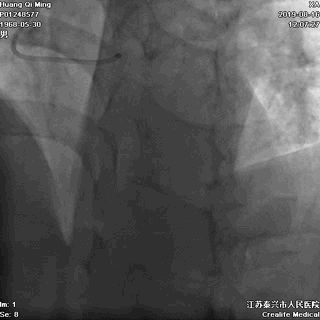

LAD PCI过程

手术器械:

7F EBU3.5

0.014“ Runthrough NS

2.0*20 Maverick

2.5*10 切割球囊

2.5*12 Quantum Maverick球囊

2.0*25 药物洗脱球囊

2.5*25 药物洗脱球囊

导丝通过病变抵达血管远段

8atm,2.0*20球囊行PTCA

8atm,2.0*10 切割球囊对斑块进行切割

16atm,NC球囊对斑块进行预处理

2.0*25 药物洗脱球囊,8atm*60秒释放药物

2.5*25 药物洗脱球囊,8atm*60秒释放药物

术后即刻效果满意